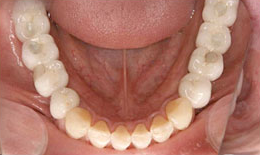

インプラント症例(1)30代 女性

治療後

上顎

保存困難な歯を抜歯後、インプラントを7本埋め込み、セラミックスクラウンを被せた

下顎

保存困難な歯を抜歯後、インプラントを6本埋め込み、セラミックスクラウンを被せた